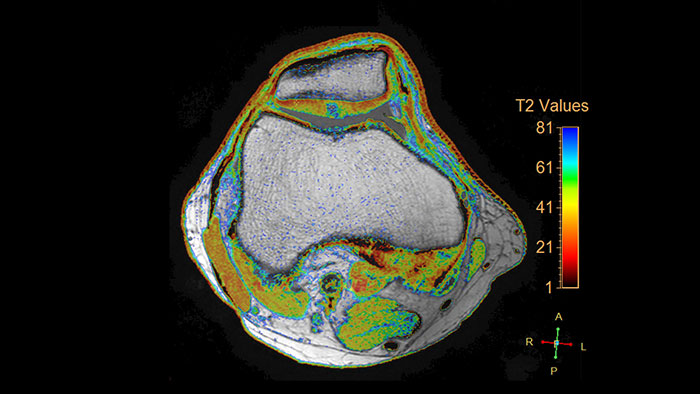

Visualize cartilage structures

Enables the visualization of cartilage structures integrated with color-coded T2 maps. Positioning of cartilage-shaped, layered region of interest is used to assess variation of T2 values across the cartilage depth to determine the degradation of the cartilage.

Benefits